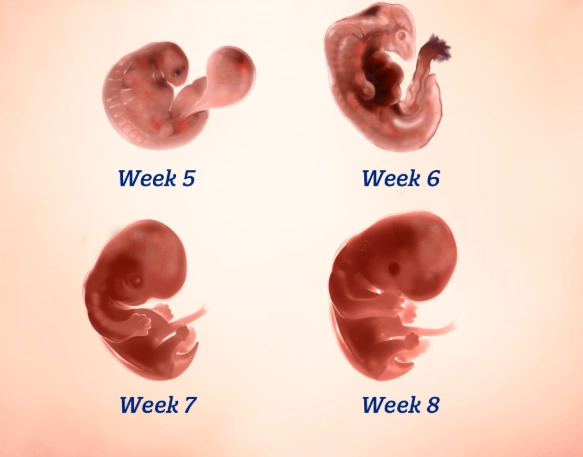

First, a tiny bit of science to ground us. At four weeks pregnant, you're technically in the second half of your first month. Conception happened about two weeks ago. Right now, the fertilized egg has travelled and implanted itself in your uterine lining. It's now called a blastocyst, and it's busy dividing like crazy. The part that will become the placenta is starting to form and produce the pregnancy hormone hCG (human chorionic gonadotropin).

Don't expect a baby bump. Your uterus is still tucked deep inside your pelvis. You also won't feel the baby move—that comes much later, around 16-25 weeks. The absence of dramatic symptoms doesn't mean anything is wrong. Every pregnancy is unique.